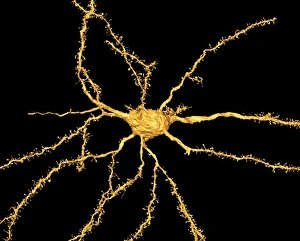

The central nervous system, the intricate network that governs our every thought and movement, is a marvel of complexity. From the delicate cerebellum tissue to the detailed light micrograph capturing its essence, we are reminded of its importance in maintaining balance and coordination. Anatomy comes alive as we explore the human brain from an inferior view. The intricacy of brain fibers is revealed through DTI MRI scans like C017/7099 and C017/7035, showcasing their vital role in transmitting information throughout this extraordinary organ. Artistic renderings bring us closer to understanding the medulla oblongata's significance within the brain. Its portrayal in various artworks allows us to appreciate how it controls essential functions such as breathing and heart rate. As we delve deeper into studying the central nervous system, models of the human brain provide invaluable insights into its structure and organization. Lateral views reveal countless regions responsible for cognition, emotion regulation, sensory perception, and motor control. Microscope slides offer glimpses into nerve cells' intricate architecture—a testament to their ability to transmit electrical signals at lightning speed. Meanwhile, glial stem cell cultures captured under a light microscope remind us of their crucial role in supporting neuronal function. Finally, artistic representations unveil the limbic system's enigmatic nature—an interconnected web responsible for emotions and memory formation. These captivating artworks allow us to visualize this complex network within our brains. Exploring these hints provides a glimpse into the awe-inspiring world of our central nervous system—the very foundation upon which our thoughts, actions, memories reside—reminding us just how remarkable our brains truly are.